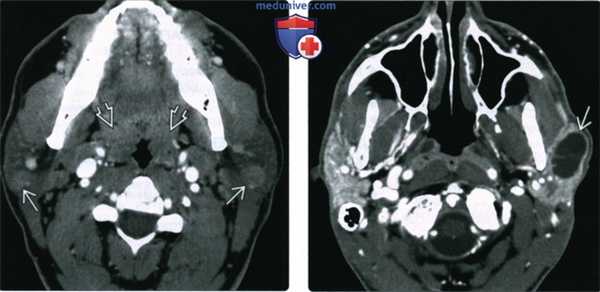

(Слева) Классическая картина доброкачественного лимфоэпителиального поражения околоушных желез при ВИЧ. В обеих околоушных железах обнаруживаются кистозные и солидные лимфоидные образования. Обратите внимание на гипертрофию лимфоидной ткани глоточной миндалины. Реактивная лимфаденопатия (здесь не показана) также весьма характерна для доброкачественного лимфоэпителиального поражения.

(Справа) КТ с КУ, аксиальная проекция. У ВИЧ-пациента в обеих околоушных железах (их плотность повышена) определяются множественные микрокисты. Такая картина характерна для доброкачественного лимфоэпителиальною поражения. Обратите внимание на гипертрофию глоточной миндалины. (Слева) КТ с КУ, аксиальная проекция. Крупные многокамерные кисты в обеих околоушных железах у пациента с ВИЧ. Внутри кисты видны перегородки.

(Справа) КТ с КУ, аксиальная проекция. Двусторонние кистозные образования околоушных желез с узловатым строением стенок (лимфоидные фолликулы) у пациента с ВИЧ. При доброкачественном лимфоэпителиальном поражении в железах могут возникать как кисты, так и солидные объемные образования. Обратите внимание на гипертрофию небных миндалин.